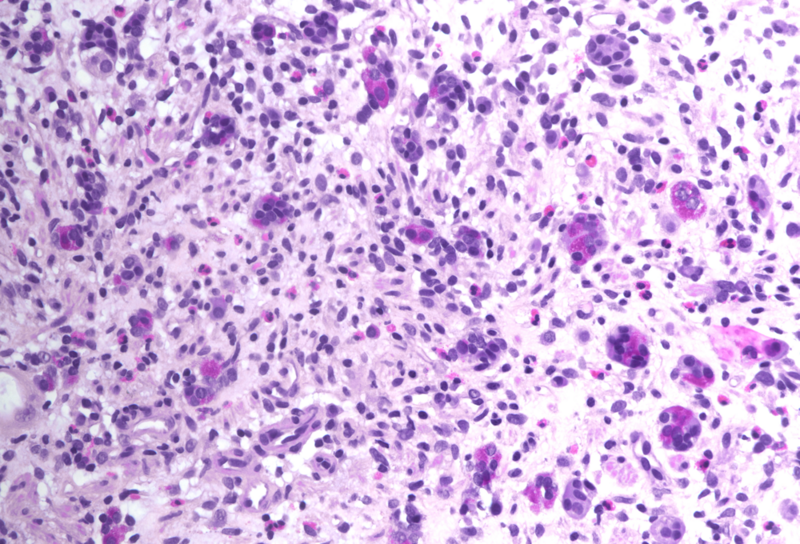

Histology showed an extremely altered gastric mucosa, with architectural distortion by glandular atrophy, degenerative epithelial changes, erosions and an expanded oedematous lamina propria (PANEL A-C). On higher magnification, the lamina propria contained a mixed inflammatory infiltrate, characterized by lymphocytes, plasma cells, eosinophils and neutrophils, focally with abscess formation. We observed withering glands lined by flattened eosinophilic epithelium, occasionally containing apoptotic debris (PANEL D-E); in other areas, little atrophic neuroendocrine nests were found (PANEL F). In summary, there was a severe acute inflammation and signs of acute epithelial injury highly suggestive of a drug-induced gastritis, consistent with injury due to pembrolizumab.